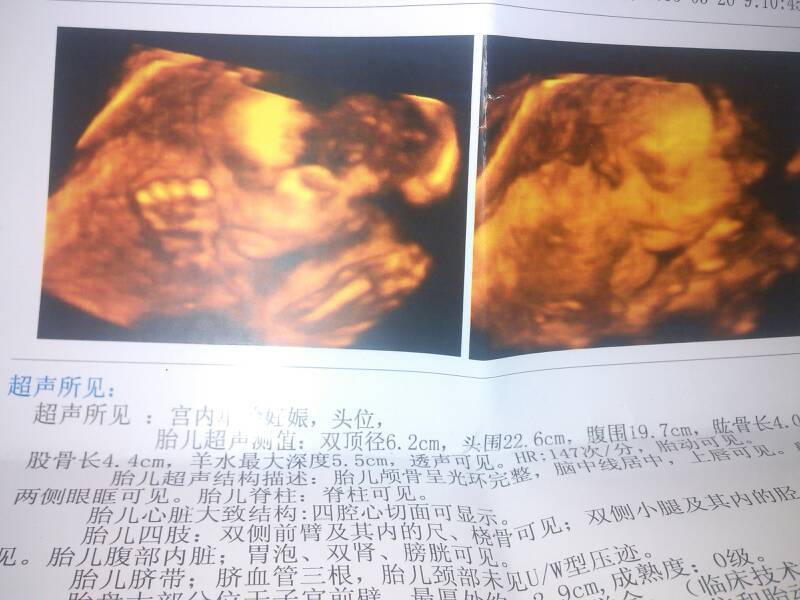

亲,四维彩超顺利回来,有经验的宝妈能帮我看看男女么? 亲,四维彩超顺利回来,有经验的宝妈能帮我看看男女么? 点击展开 SHI DP.@ 2015-03-26 12:11 为您推荐: 其他回答 看不出的!!!!! Jonny太 2015-03-26 14:05 有点像女宝 156*****218 2015-03-26 13:25 单子看不出差 月光影 2015-03-26 12:52 呵呵,看不出来 只做你的灬女人 2015-03-26 12:34 宝妈好孕, 陌上花开(¯.¯) 2015-03-26 12:24 加载更多 相关问题 四维彩超出来了 有视频 亲们帮我看看 男女谢谢 宝妈们帮我看看男女吧,祝大家好孕 宝妈们,,,医生们,都帮我看看